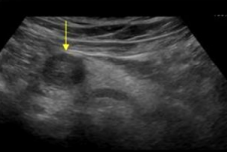

Describe this image

Dx?

A well-defined, hypoechoic, complex mass located in the head of the pancreas

Dx: adenocarcinoma